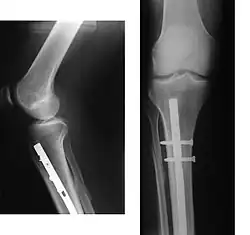

Fracturas

Las fracturas de la región de la rodilla pueden afectar a la porción inferior del fémur, la superior de la tibia o la rótula. Con frecuencia son fracturas complejas que afectan a varios huesos y a los meniscos o ligamentos. Generalmente están causadas por un gran impacto, como ocurre en los accidentes de tráfico. En la mayoría de los casos deben ser tratados quirúrgicamente por osteosíntesis, por lo general con el uso de piezas de acero o de placas y tornillos de titanio. A menudo también se requiere reconstruir la superficie articular con materiales óseos o de cerámica. Las fracturas puras pueden ser fijada solo con tornillos.

Las fracturas de la extremidad inferior del fémur pueden ser supracondíleas, si se producen por encima de los cóndilos o bien afectar al cóndilo externo, al interno o a ambos. Las de la extremidad superior de la tibia pueden afectar a la meseta tibial externa, a la interna o a ambas.

Las fracturas de rótula son infrecuentes y suelen ocurrir por caídas con impacto directo sobre este hueso. Pueden ser longitudinales, transversales o compuestas. Tienden a dejar fragmentos que pueden causar limitación en la movilidad de la articulación.[30]